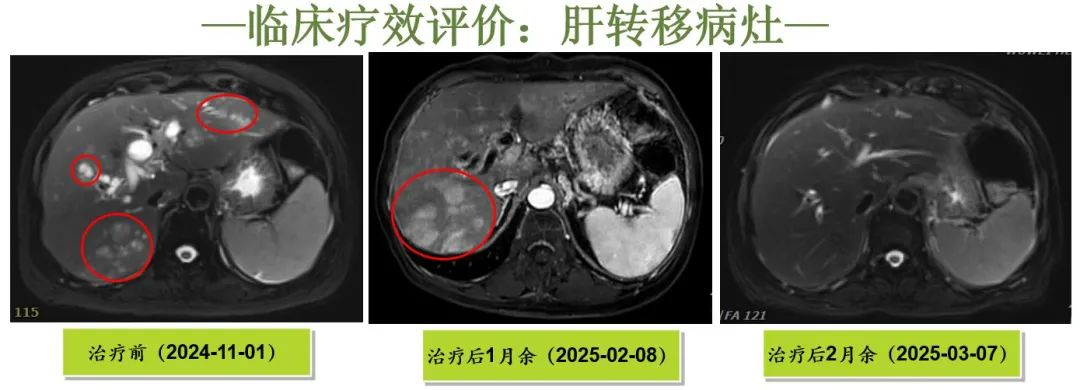

[Efficacy Evaluation]

CR(Complete Response):